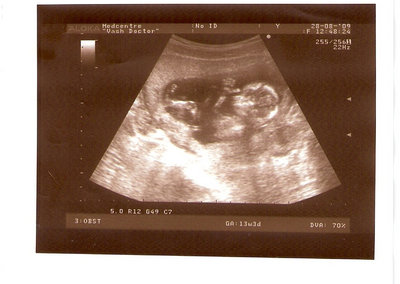

СЫН

| Вложения: |

2.jpg [ 110.14 КБ | Просмотров: 2449 ]

Foto prosto chudesnoe. A na kakom sroke uznali, chto sin..............

Nikisa писал(а): Foto prosto chudesnoe. A na kakom sroke uznali, chto sin.............. НА 13 НЕДЕЛЯХ.КАК РАЗ ВОТ В ЭТО узи, ОНО УМЕНЯ ВТОРОЕ БЫЛО. ЭТО КОНЕЧНО МАЛЕНЬКИЙ СРОК ДЛЯ ОПРЕДЕЛЕНИЯ ПОЛА. НО Я ПОПРОСИЛА ВРАЧА(ЭТО КТСТАТИВ РОССИИ БЫЛО) ХОТЯ БЫ ПРЕДПОЛОЖИТЬ. ЕЙ ВСЁ ТАКИ УДАЛОСЬ РАССМОТРЕТЬ.НУ ВООБЩЕМ ЧЕРЕЗ НЕСКОЛЬ ДНЕЙ ПОЙДУ К ВРАЧУ, УЖЕ АМЕРЕКАНСКОМУ И УЗНАЮ ТОЧНО. К ТОМУ ВРЕМЕНИ У МЕНЯ БУДЕТ СРОК 18 НЕДЕЛЬ. ХОТЕЛОСЬ БЫ ПОСМОТРЕТЬ НА ДРУГИЕ ФОТО НА ЭТОМ СРОКЕ ИЛИ БОЛЬШЕ. ТАК ЧТО ВЫКЛАДЫВАЙТЕ, ЕСЛИ НЕ ЖАЛКО!